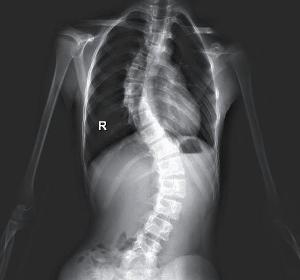

一种脊柱结构性的侧弯,生长发育期间原因不清楚的脊柱侧凸称为特发性脊柱侧凸。60%~80%的病例发生在女孩中,10~16岁儿童中有2%~3%可察觉到脊柱侧凸。当一侧肩胛似乎比另一侧高时,或衣服不能拉直时,可能会首次怀疑到有脊柱侧凸,但更多的是在体格检查中查出的。最早的主述可能是长时间坐或站后腰部无力,随后是紧张区域的背部肌肉性疼痛。